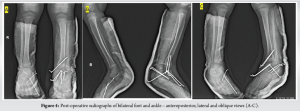

Initial management included immobilization with a below-knee slab and analgesia with paracetamol. Cryotherapy was administered using ice application for 10 min, 3 times daily to reduce swelling and discomfort. Following stabilization, the patient was taken to the operating theatre for definitive surgical treatment under general anesthesia. On the left side closed reduction and percutaneous fixation using K-wires was performed for the distal tibial physeal injury using two 2.0 mm K-wires. In addition, the talus was stabilized with two 2.0 mm K-wires, and the calcaneus was fixated using three 2.0 mm K-wires. A below-knee slab was applied post-operatively for immobilization. On the right side closed reduction and percutaneous fixation using K-wires was performed for the Lisfranc injury, with two 1.5 mm K-wires and conservative for right side talus fracture. A below-knee slab was applied for post-operative immobilization. (Figure 4), Post-operative recovery was uneventful, and the patient was monitored closely for signs of neurovascular compromise, infection, and appropriate healing.

The patient was reviewed regularly in the outpatient department, with close observation of recovery progress. Kirschner wires were removed at 6 weeks post-surgery, and the below-knee immobilization was maintained for a total of 8 weeks. After slab removal, the patient began a supervised physiotherapy program focusing on ankle range of motion exercises, continued over the next 4–6 weeks. Gradual weight-bearing with the assistance of a walking frame was initiated at this stage. By the 4th post-operative month, the patient was ambulating independently without support, and radiographs confirmed satisfactory fracture union (Figure 5,6),. At the 5-month follow-up, ankle mobility had returned to near-normal levels, with both dorsiflexion and plantarflexion ranging from 0 to 15° bilaterally. Further follow-up at 15 months revealed normal range of motions at bilateral ankle (0–15° of plantar and dorsiflexion) with foot and ankle outcome score being 95% (Figure 7-9).